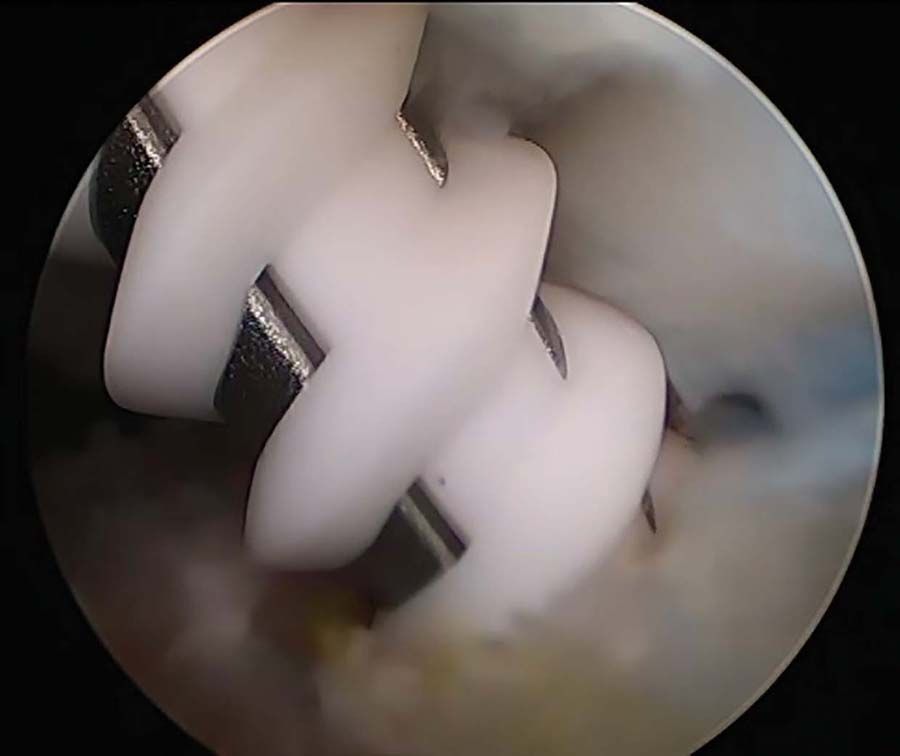

Technique Arthrolyse arthroscopique pour raideur sur prothèse totale du genou , François Kelberine Pôle Aixois de Chirurgie Articulaire et Sportive (PACAS) - Clinique Provençale Parc Rambot, Aix en Provence, France 🖂 fkelberine@pacas.fr , Jean-Philippe Vivona Pôle Aixois de Chirurgie Articulaire et Sportive (PACAS) - Clinique Provençale Parc Rambot, Aix en Provence, France N°270 - Janvier 2018 ● 8 min de lecture